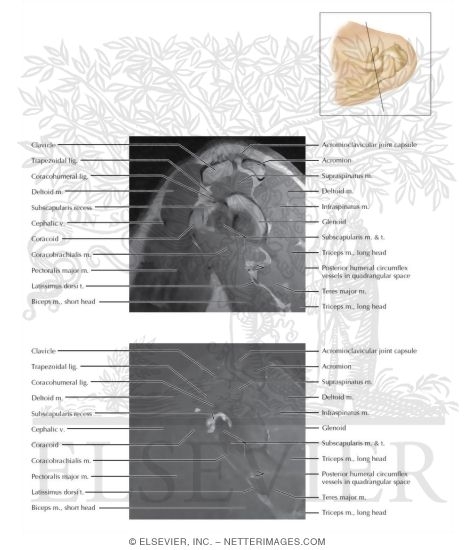

Cross Section of the Shoulder: Sagittal View

Shoulder Sagittal 10

Labeled - Major Correlative Imaging 1E